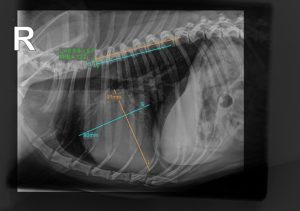

Canine Cardiac Disease Made Clear: Staging Mitral Valve Disease and Diagnosing DCM

• Overview of the ACVIM staging scheme for mitral valve disease

• How to diagnose stage B1, B2 and C

• Which tests to run, when